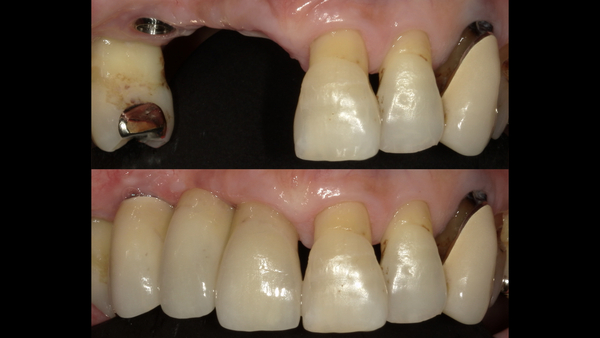

こちらが初診時のお口の中の写真となります。

右上の前歯の差し歯が取れてしまい、根っこだけが残ってしまっている状態です。

右下・左下にも同じように根っこだけの歯がいくつかあります。

こちらがセット後の写真になります。

奥歯にインプラントを入れたことで奥歯でしっかり食事が噛めるようになり、患者様は大変喜ばれておりました。

また、しばらくなかった前歯もとても綺麗に入り、大変満足されております。